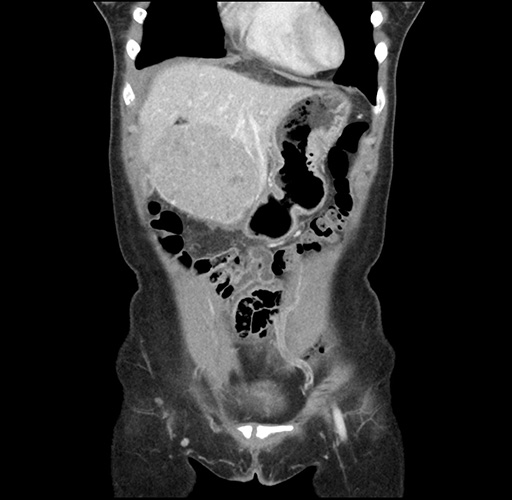

Imaging Analysis

Look through the patient's CT scan to identify any areas of concern for the necessary procedure.

Based on your CT findings, which issue(s) would give reason for "planned slowing down moment(s)" in this case?